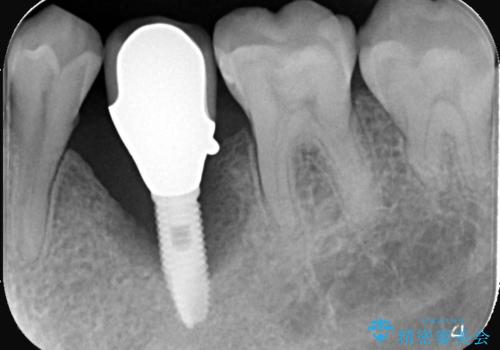

- 20年振りの来院で下顎左右5番にインプラント入れていた患者様です。

右下5番のインプラントは問題ありませんでしたが、左下5番のインプラントがインストール周囲炎に罹患している状態でした。

インプラントを抜去後、再びインプラントで治療を行いました。

20年以上振りのご来院でした。

インプラントは虫歯にはなりませんが、しっかりケアをしないと歯周病にはなってしまいます。

歯周病は歯の病気ではなく、骨の病気なので歯やインプラントは骨に支えられているため進行すると揺れてきてしまいます。